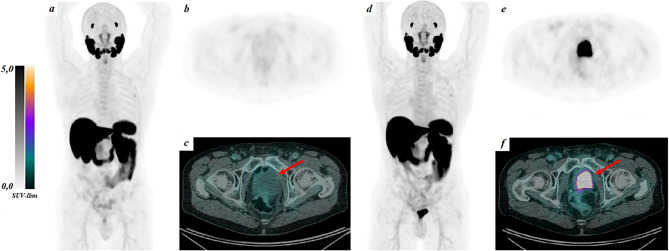

The impact of patient hydration and forced diuresis on [18F]PSMA-1007 urinary bladder uptake in PET/CT imaging.

患者水化和强制利尿对PET/CT成像中PSMA-1007膀胱摄取的影响[18F]